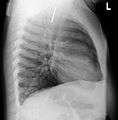

A coin seen on lateral CXR in the esophagus

Lateral X ray showing a 9mm battery in the intestines